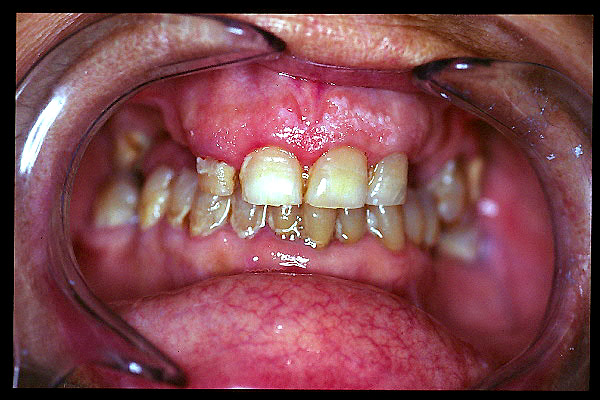

CM Placa bacteriana